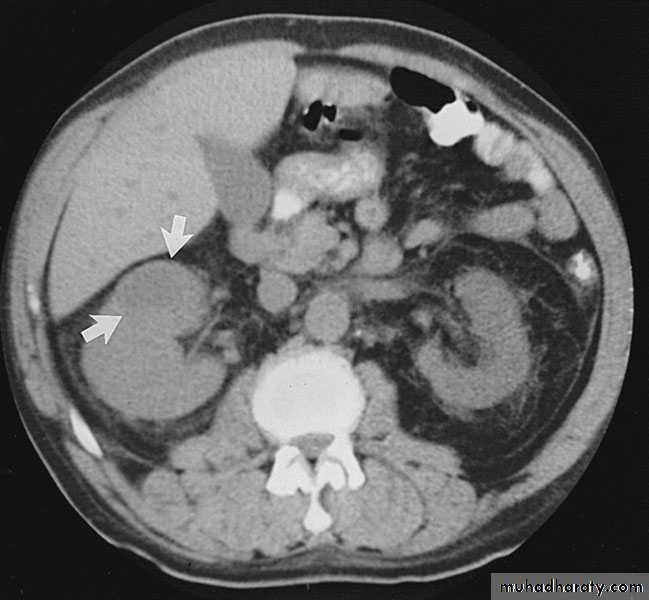

Pyonephrosis

Pyonephrosis refers to infected hydronephrosis where the kidney is converted into a sac containing pus associated with suppurative destruction of the parenchyma of the kidney, in which there is total or nearly total loss of renal function.It is usually unilateral

Investigations

GUE + C&S + blood C&SCBC

KUB

U/S

IVU

CT scan